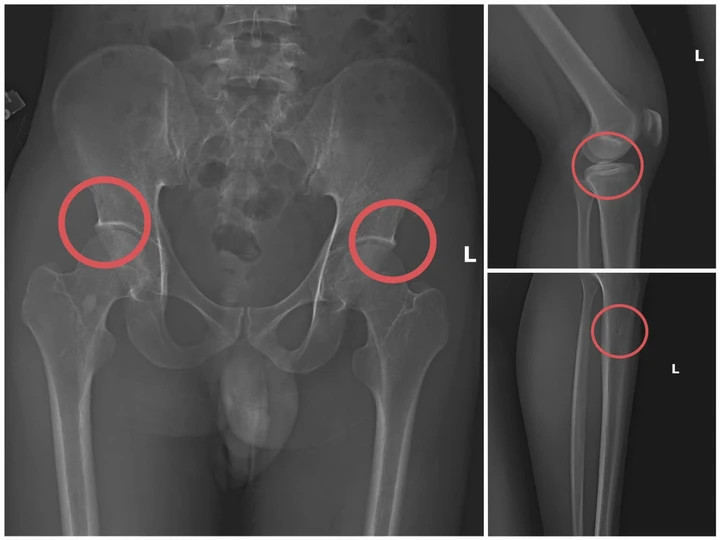

Bản phim chụp XQ một số tổn thương xương do đối tượng tạo ra. (Ảnh: Công an tỉnh Phú Thọ).